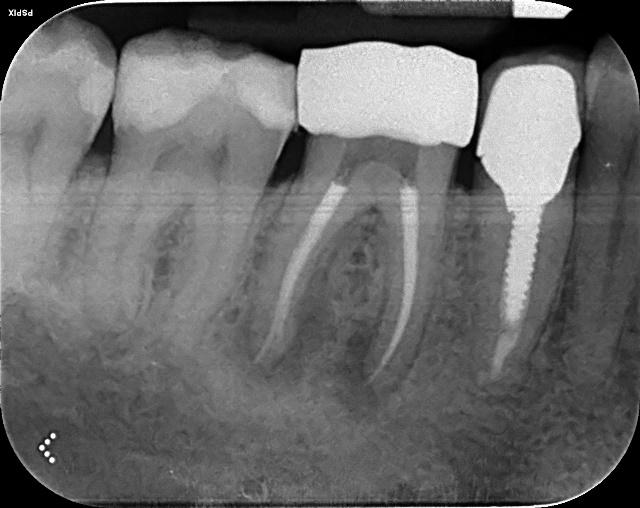

Lower Re-root canal treatment through dental crown